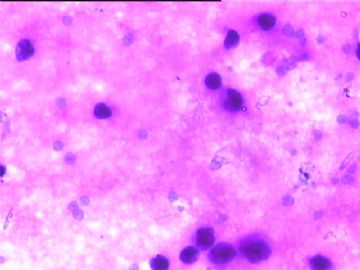

78y,男,胸水。 大家看看那些小于淋巴细胞的东东。

孢子?

图6感觉象是污染的孢子之类的东西。好好回忆一下,制片过程?容器?有没有污染的 可能?

但,最后一图的组织细胞内吞噬现象,怎么解释。

离体的细胞在一定的时间内还是活细胞,所以我推测吞噬细胞可能还是有一定的吞噬功能的。不过,确实也不能就排除了在活体内的微生物感染的可能。结合临床应该能够得到一定程度的澄清。